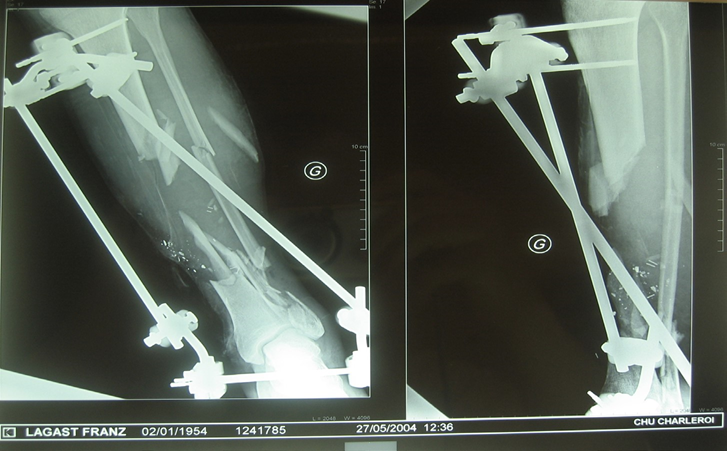

Figure 3 : “Reduction” and osteosynthesis by tibio-calcaneal external fixator was immediately performed.

Figure 11, 12 : Our final choice was for a contralateral tibial rod.

The graft was implanted centromedullary to fill the gap between the two tibial extremities, bridging the loss of substance in addition of spongy grafts. The two surgical approaches were closed by simple suture.

Figure 13 : The original fixator was kept in place for the necessary time with no local complications.